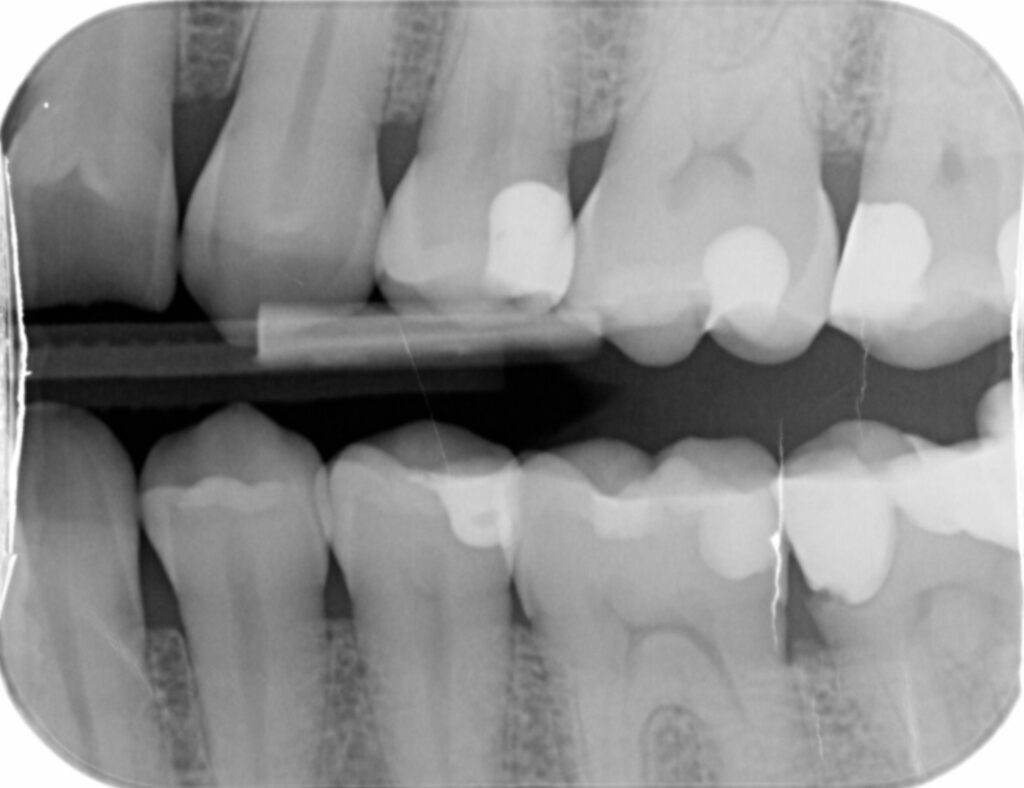

In deze cursus komt zeer uitgebreid de theorie aan bod over Röntgen. Onder andere het ontstaan, hoe röntgen werkt, welke regelgeving er is. Daarna komt de praktijk aan bod. Het maken van solo’s en bitewings wordt geleerd, maar ook het maken van de OPT en RSP, en we leren te beoordelen wat een goede foto is.

De oorsprong en theorie van röntgen, de toepassingsmogelijkheden, de negatieve invloed van röntgenstraling op het menselijk lichaam en contra-indicaties voor het maken van röntgenfoto’s, instelapparatuur en het gebruik hiervan, het maken van correcte solo’s en bitewings, en mogelijke fouten hierbij, het maken van correcte OPT’s en RSP’s en mogelijke fouten hierbij.